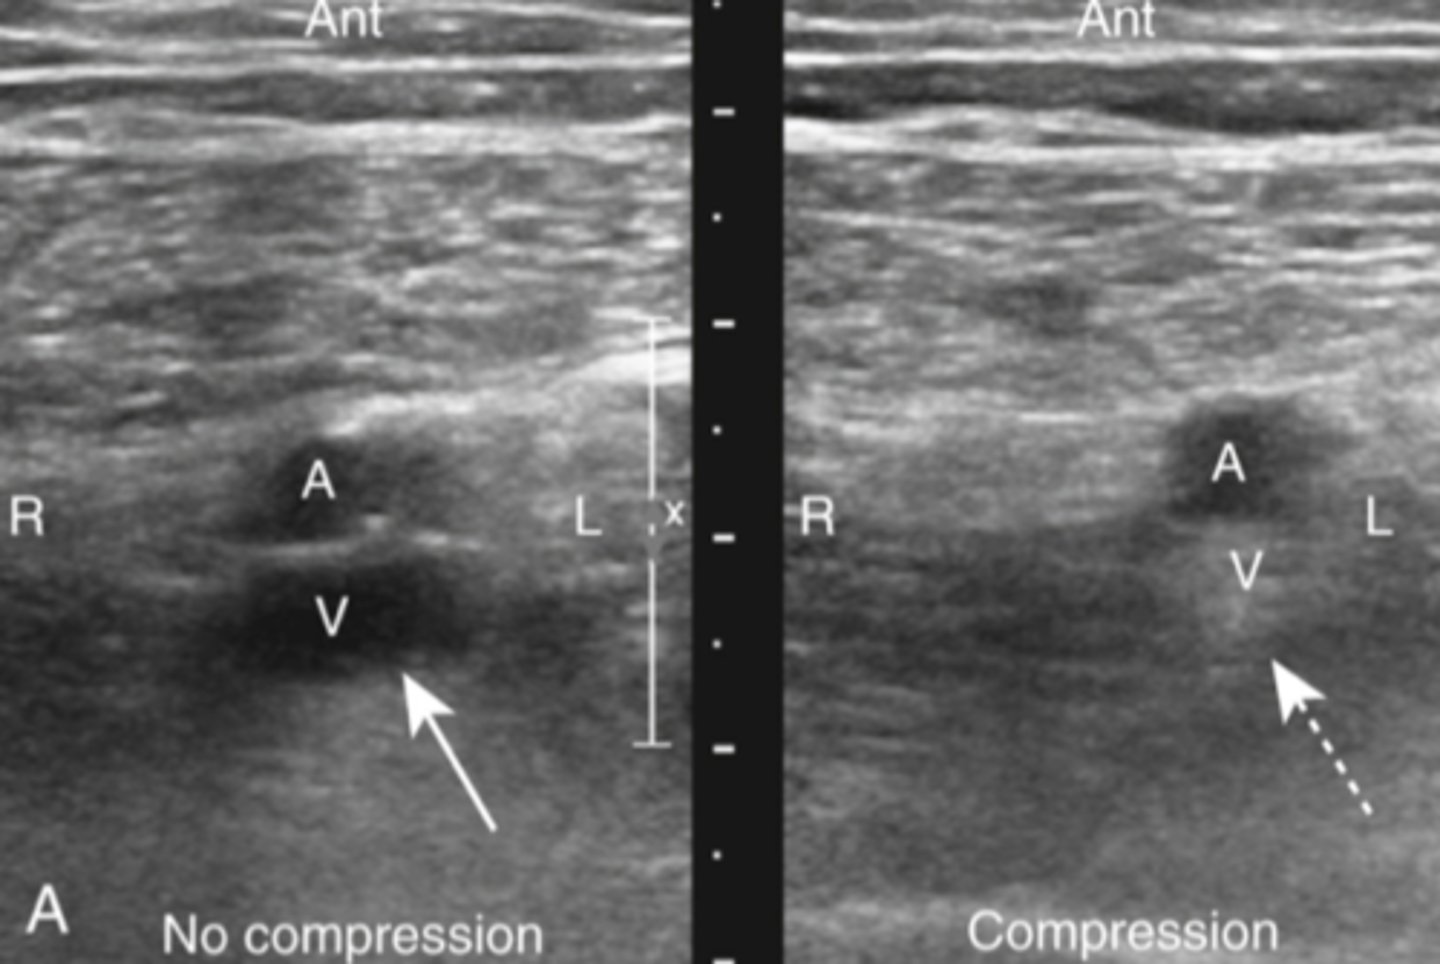

can ID DVT (assoc with PE)

can visualize the thombus directly, otherwise relies on loss of vein compressability

detects change in venous flow

how can ultrasound help diagnose DVT/PE